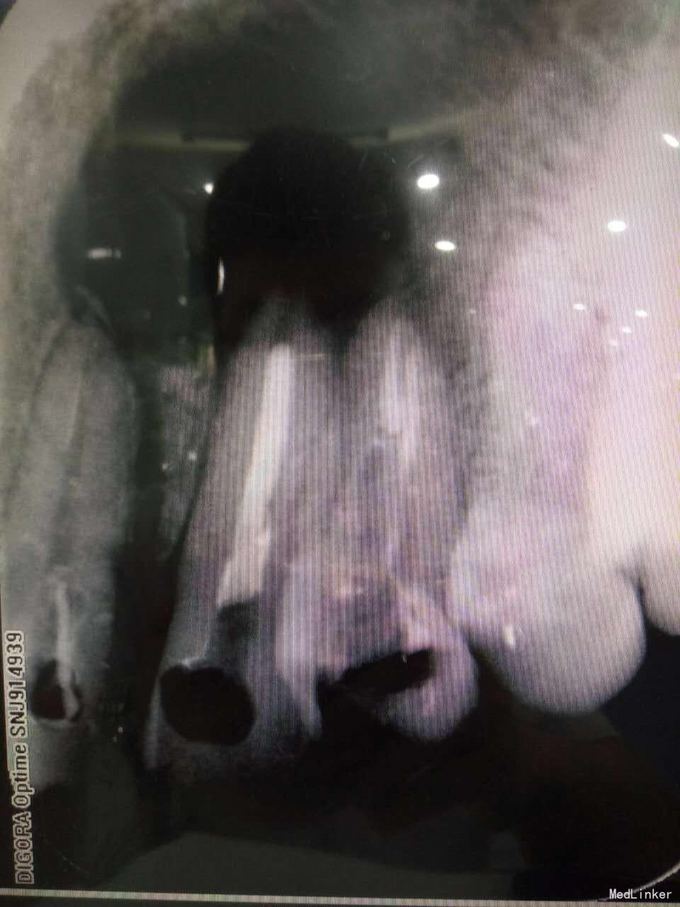

24牙合面龋坏,龋坏较深,未穿髓,龈红,无窦道,无松动 23牙牙体完整无明显松动 22牙牙体完整,腭侧有窦道,无明显松动 X线示23牙根尖牙周组织可见1cmX10cm囊肿,波及22牙及24牙

22牙牙髓部分坏死 23根尖囊肿 24牙髓坏死 1.22牙23牙24牙RCT 2.转外科行23牙囊肿摘除术 23牙MTA根尖封闭,拍片,确定根尖封闭良好,使用热牙胶垂直加压充填,流动树脂垫底,Z350树脂充填抛光 22牙24牙根充,流动树脂垫底,Z350充填抛光